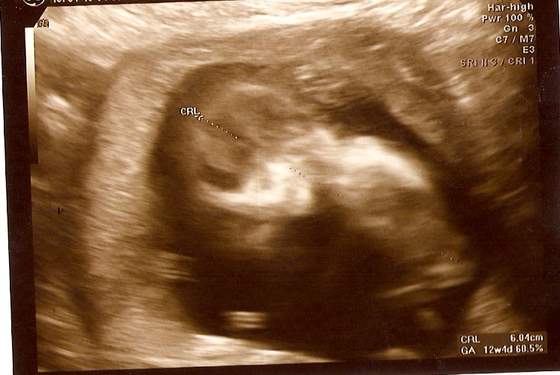

love - ja DOPIERO na 14:30 (ale i tak capnęłam pierwszy numerek, bo lekarz przyjmuje właśnie od tej godziny). Chciałabym, żeby mąż mój w końcu zobaczył i uwierzył

Ale godzina taka, że nie wiadomo czy uda mu się wyrwać z roboty, szczególnie, że następnego dnia mamy sprawę w sądzie i wziął wolne... eh...